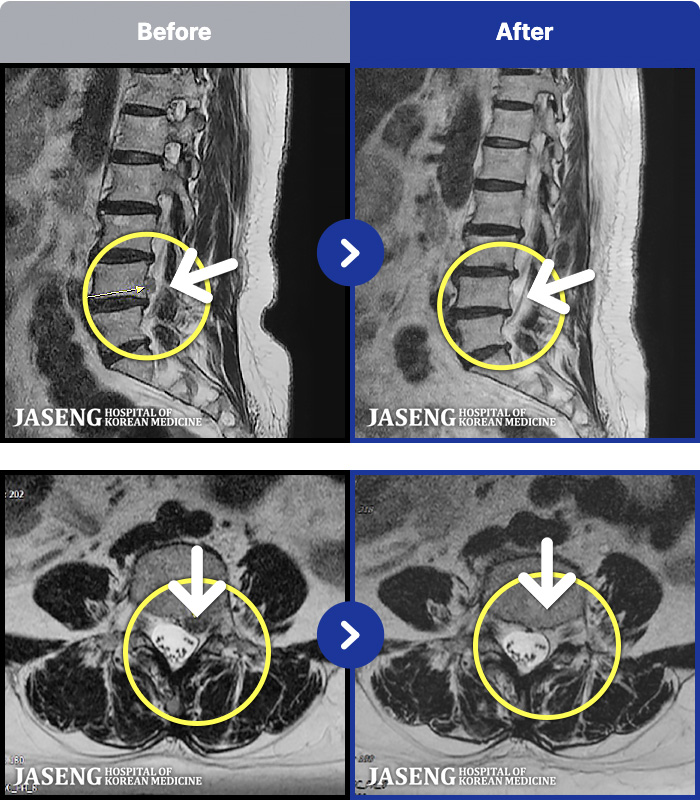

56 MRI ũ ʸ Ȯϼ.

㸮 ϻ .

[Ȼ] 23.03.13~24.05.08

ȯںп Ǹ ǿ ԿǾ, ο ġ ۿ Ƿ ġḦ Ͻñ ٶϴ.